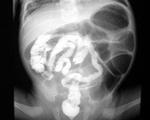

• Рентгенограмма брюшной полости. Для дуоденальной непроходимости патогномоничен симптом «двойного пузыря» - наличие двух пузырьков газа в желудке и двенадцатиперстной кишке. Врожденная низкая непроходимость проявляется множеством горизонтальных уровней жидкости, которые соответствуют чрезмерно растянутым участкам тонкой и толстой кишки.